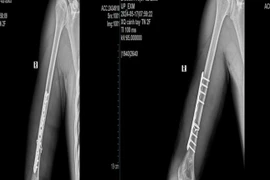

1 tuần 3 trường hợp gãy xương cánh tay từ trò chơi vật tay

Có những trường hợp nhập viện trong tình trạng gãy nham nhở, khó đưa xương về vị trí ban đầu, tổn thương các dây thần kinh quay, trụ và mạch máu lân cận.

Trong lúc thi vật tay cùng bạn bè, nam thanh niên 18 tuổi bất ngờ nghe thấy một tiếng “rắc” vang lên, kèm theo cảm giác đau dữ dội.